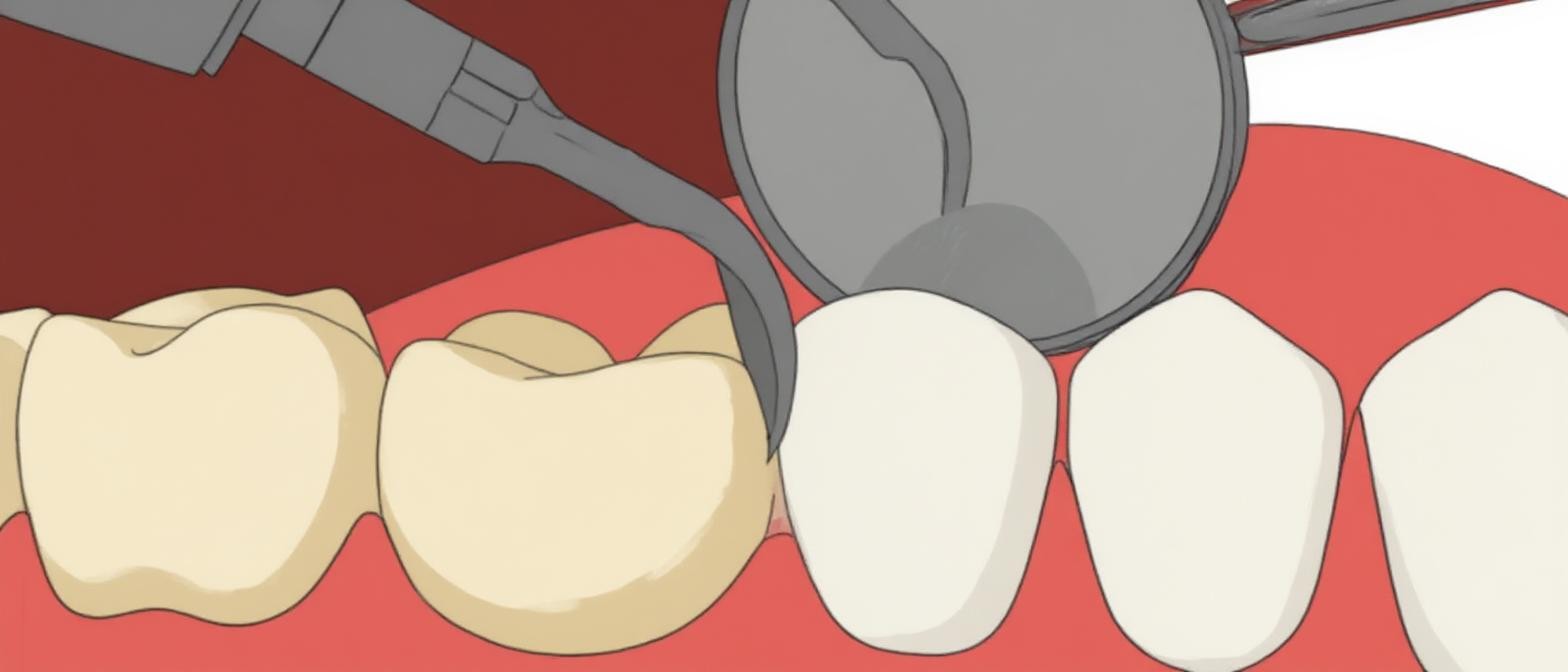

- Corona

Le corone sono restauri a forma di dente realizzati in condizioni di laboratorio che proteggono e rafforzano i denti danneggiati, migliorando allo stesso tempo l’estetica del paziente rigenerando il suo sorriso. - Ponti fissi

I ponti sono protesi fisse che sostituiscono i denti mancanti utilizzando denti artificiali per colmare il divario. Poggiano sui denti o sugli impianti vicini.

Corona Emax

Prima